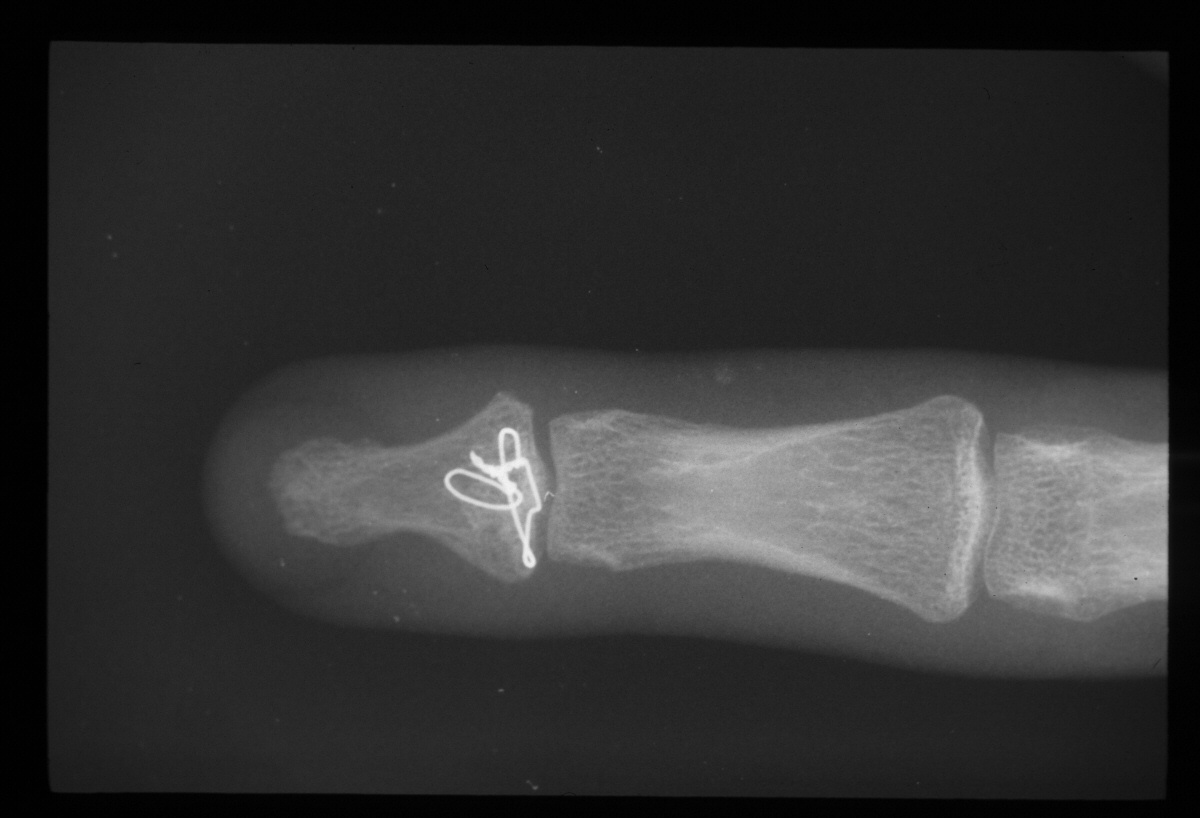

| A wire was passed through the dorsal proximal pin track and then around the palmar pins. After reduction and tightening this wire, the pins were advanced to engage the dorsal cortex. |

| Wiring was used to offset the strong pull of the flexor insertion. |

| All pins were cut below the surface of the skin. |